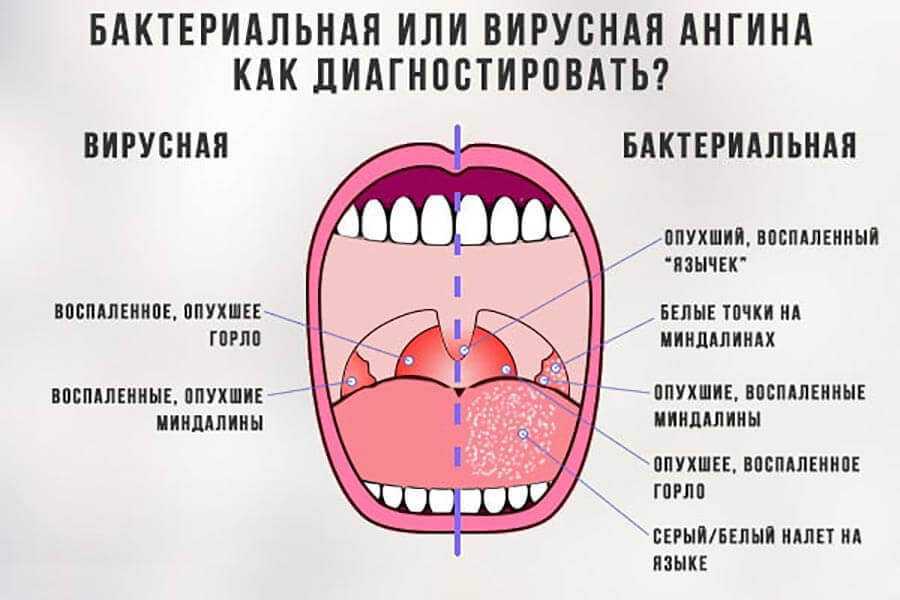

Клиническое течение при ангине у каждого ребенка может отличаться, учитывая тип заболевания:

- Катаральная, которая является наиболее распространенной и протекает легче, чем другие типы болезни. Проявляется поверхностным поражением миндалин с появлением небольших красных участков на слизистой оболочке. Симптоматика выражена не остро, при этом возможно незначительное повышение температуры до 37-38°С. Ребенку часто ставится такой диагноз при развитии заболеваний верхних дыхательных путей.

- Фолликулярная или гнойная. Отличается более острым течением, часто сопровождается высокой температурой – 38°С и выше. При подобной форме на миндалинах можно обнаружить небольшие белые или желтые гнойники не больше 2 мм. При гнойной ангине увеличиваются и болят при пальпации лимфоузлы на шее и затылочной части.

Изображение 1.1. При образовании на миндалинах участков с некрозом, глубоких язв диагностируется язвенно-некротическая форма патологии.

Проявиться разные виды заболевания могут при воздействии на небные миндалины патогенных микроорганизмов – вирусов, бактерий, грибков. У детей младшего возраста ангина преимущественно имеет вирусное происхождение, проявляясь вследствие вируса герпеса, Эпштейн-Барра, аденовируса, цитомегаловируса. У школьников заболевание возникает при воздействии стрептококков, стафилококков, грибков, спирохет, пневмококков. Здоровый детский организм способен противостоять воздействию инфекции. Заболевание развивается при ослаблении иммунной системы на фоне переохлаждения, усиленных физических нагрузок, частых стрессов, несбалансированного питания, рецидивирующих респираторных заболеваний.

Причины бактериальной ангины у детей

Бактериальная ангина представляет собой инфекционное заболевание, при котором возникает воспаление ткани небных миндалин в результате попадания на них патогенных микроорганизмов, либо увеличения числа условно-патогенных микроорганизмов. Они проникают воздушно-капельным путем от инфицированного человека к здоровому при кашле, чихании, при использовании одних и тех же столовых приборов, полотенец и др.

Еще одним очень важным фактором риска развития микробного поражения миндалин является наличие у ребенка острого респираторного вирусного заболевания. Вирусно-бактериальная ангина у ребенка встречается очень часто. В данном случае врачи придерживаются мнения, что лечить необходимо более тяжелое заболевание, а именно бактериальный тонзиллит.

Наиболее часто бактериальная или гнойная ангина у детей вызывается бета-гемолитическим стрептококком группы А. Причина заключается, прежде всего, в его строении: они несут капсулы (М-белок) для адгезии к слизистой оболочке миндалин. Эти микроорганизмы устойчивы к фагоцитозу и выделяют различные экзотоксины. Последние приводят к выработке антител, которые перекрестно действуют еще и на сердечную мышцу, ткань сосудов, суставов и почечную паренхиму.